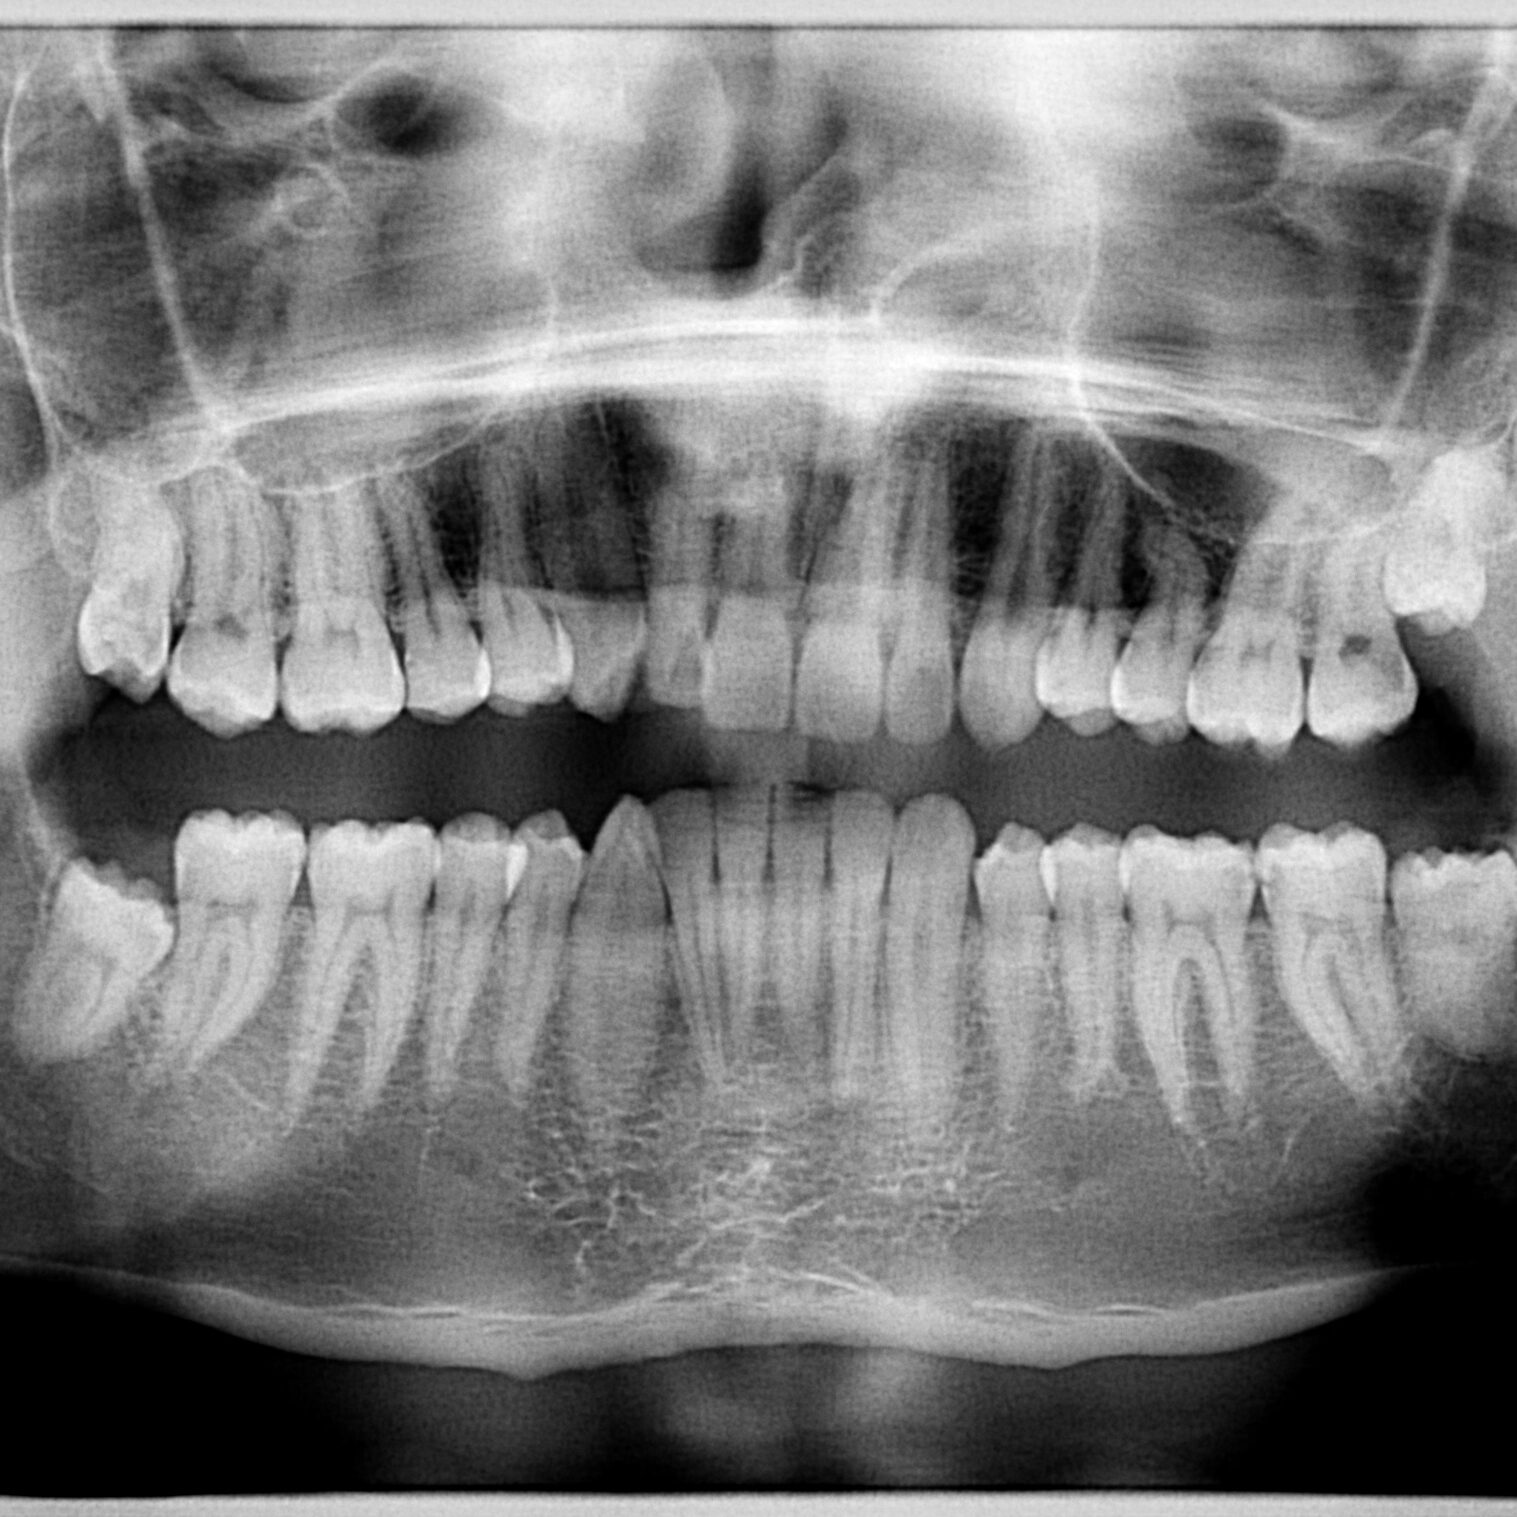

Orthopantomogram

X-ray panoramic two-dimensional image of the jaw that enables quick and easy diagnosis of almost all dental problems.

In addition to the classic orthopantomogram, a bitewing scan and scans of the maxillary sinuses and temporomandibular joint are also available.